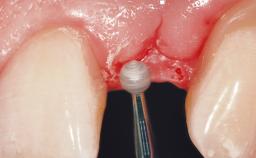

Immediate Flapless Placement of an Implant in a Maxillary Left Central Incisor Site

A 42-year-old female patient was referred to our clinic at the School of Dentistry of the University of São Paulo in November 2004, presenting a deficient restoration in the upper left central incisor. The clinical examination revealed no gingival retraction or any signs of gingival inflammation and, therefore, previous periodontal treatment was not considered. The patient presented a high lip line at full smile and a thin tissue biotype. This combination characterized a high-risk situation from an anatomic point of view, which required careful preoperative planning and cautious surgical execution.

| Soft Tissue Contour and Volume | Ideal |